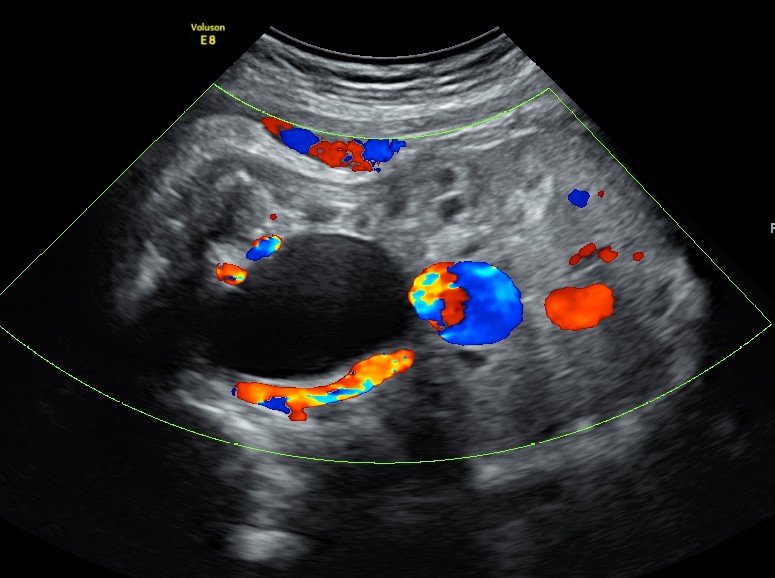

The scan was done around the 35 weeks.The following images were seen .

The differential diagnosis : urachal or ovarian cyst ; easily differentiated with the Doppler examination.

An umbilical varix is a developmental rather an embryologic abnormality and most cases have a normal ultrasound at 16 to 19 weeks gestation.

Unlike persistent right umbilical vein, umbilical vein varices have not been associated with other congenital malformations.

The significance of an antenatally detected umbilical varix remains controversial.

This finding has been associated with an unexplained high mortality rate in utero: thrombosis of the dilation leading to fetal death and other complications including hydrops fetalis. It had also been linked with chromosomal abnormalities.

Karyotyping is not warranted if not any associated malformation is detected.

When a fetal intra-abdominal umbilical vein varix is isolated, a good fetal outcome is expected.